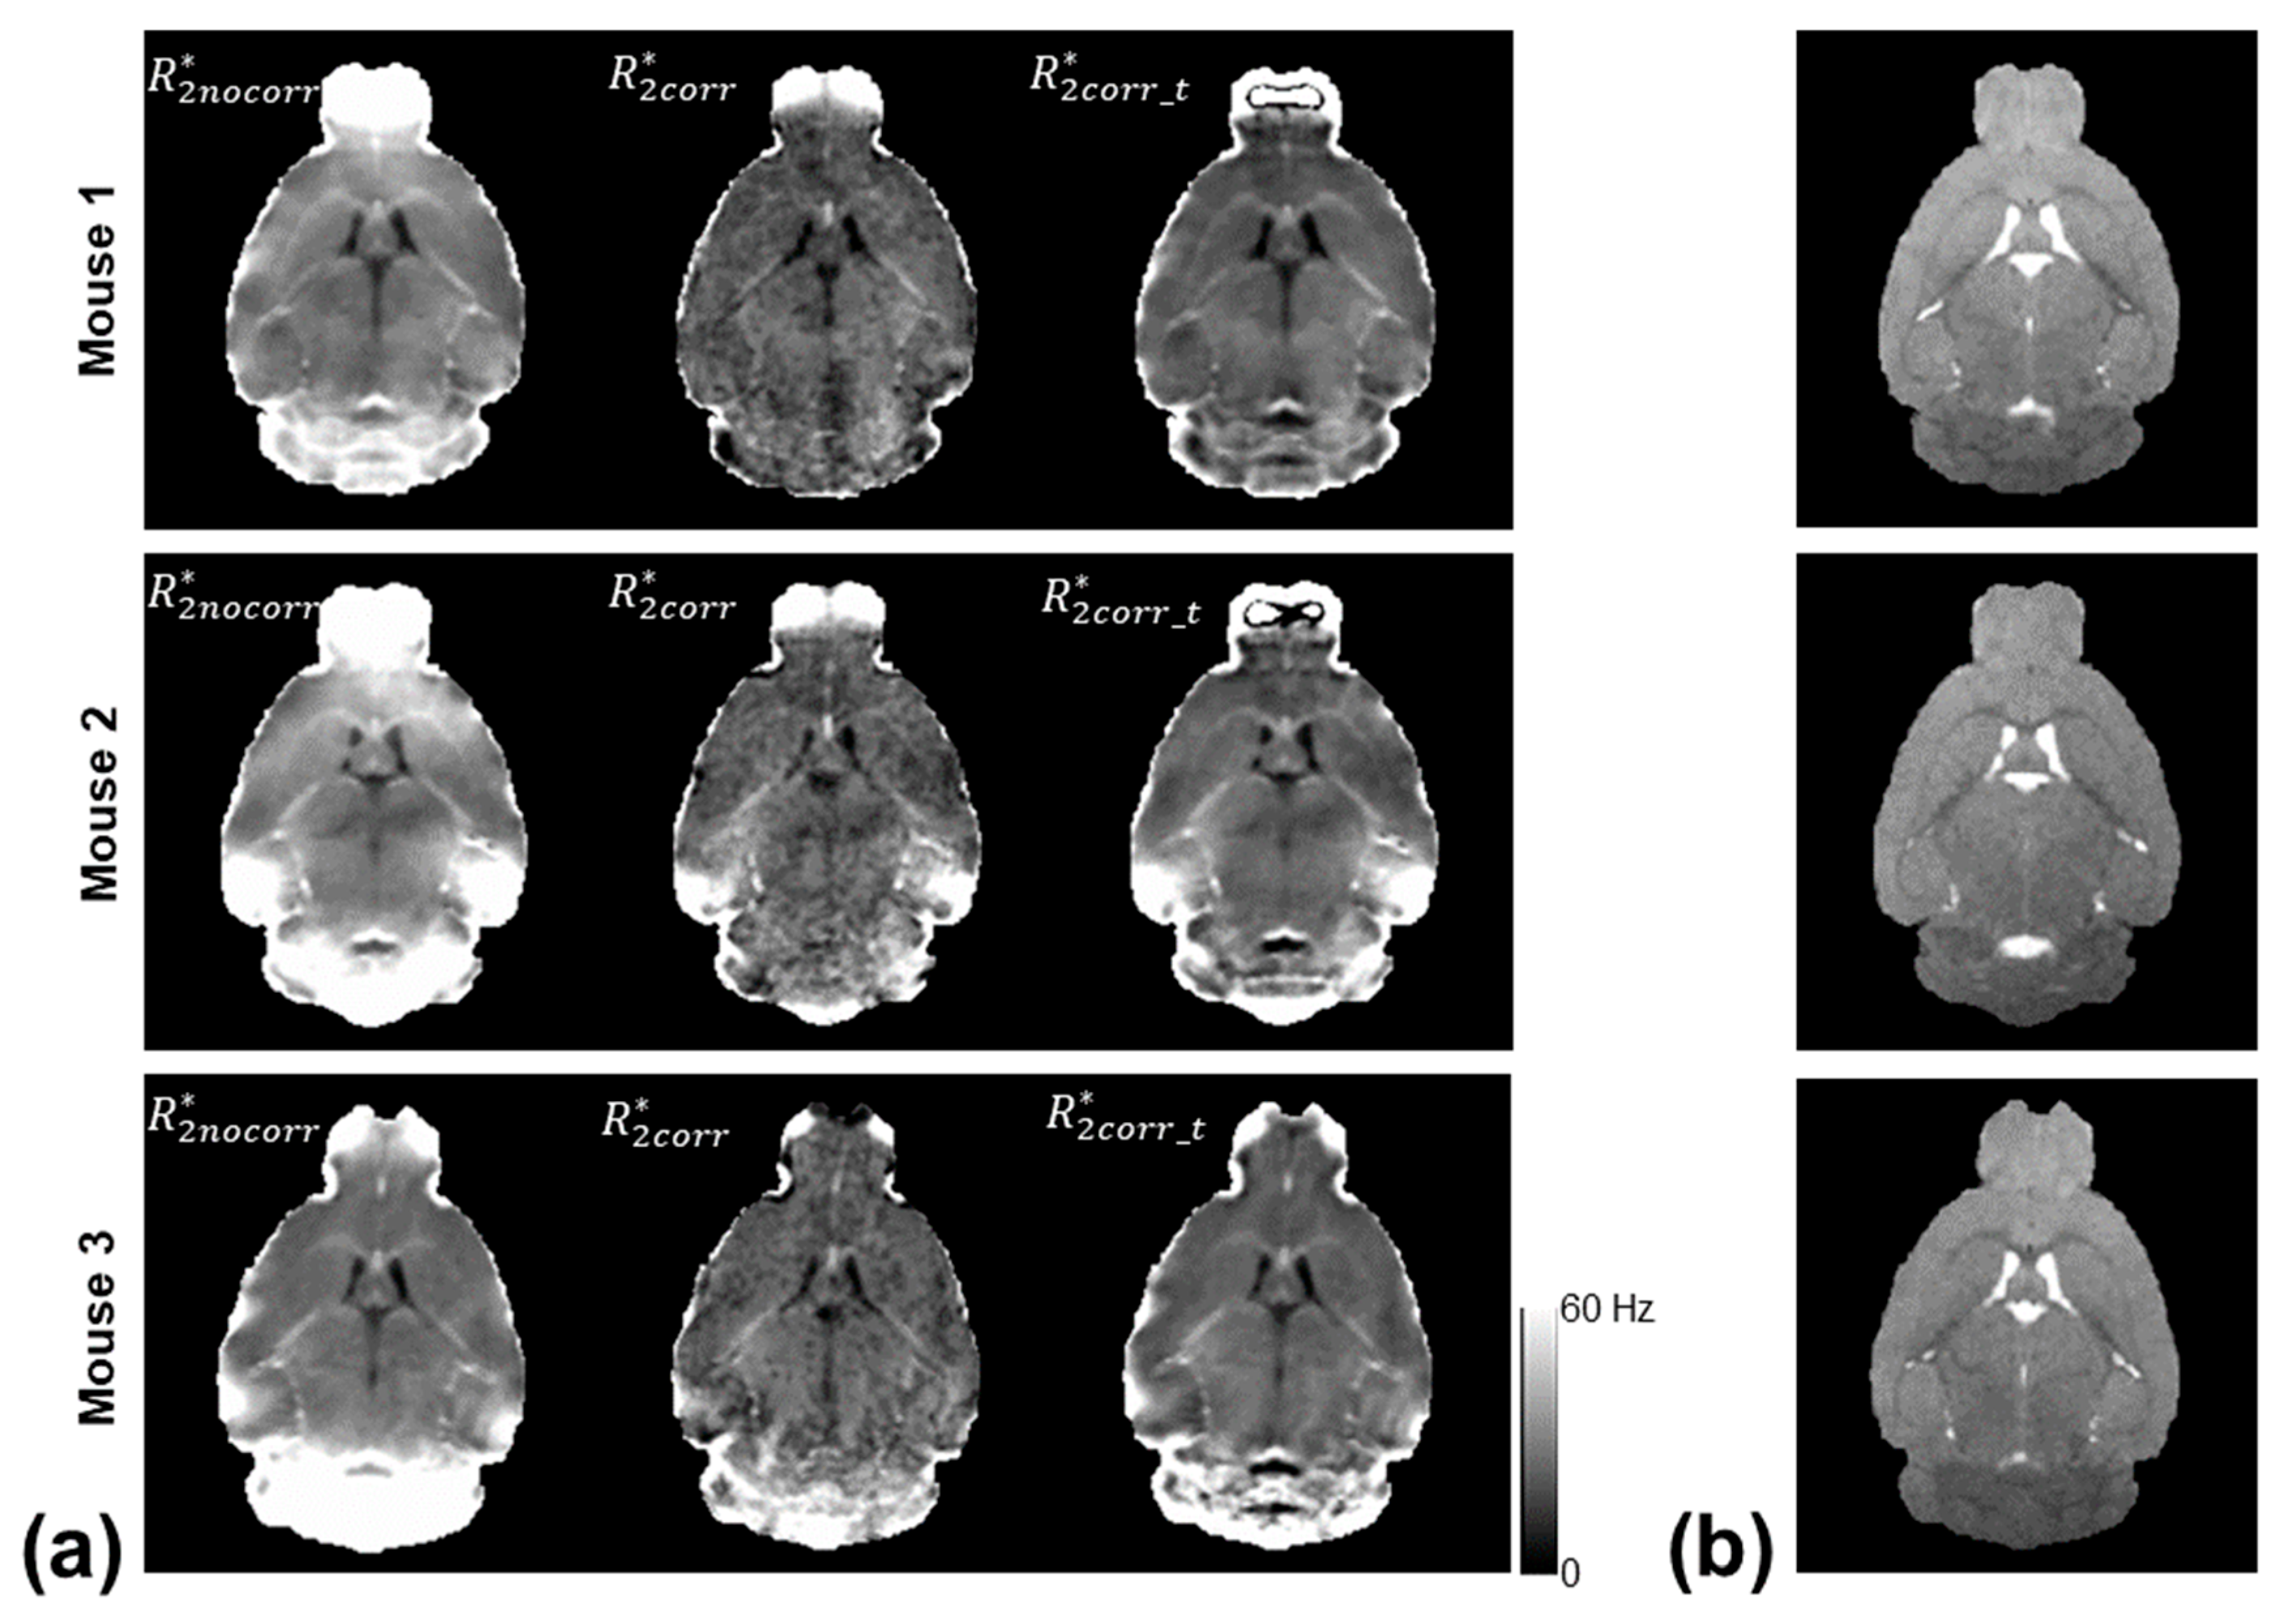

Figure 2 shows the computed R 2 n o c o r r * , R 2 c o r r * , and R 2 c o r r _ t * maps of three mice using the monoexponential model, three-parameter model, and two-stage fitting procedure. Figure 3 shows the corresponding χ ν 2 maps using the three fitting methods. R 2 n o c o r r * showed the ΔB0-induced increases in the regions near air–tissue interfaces, where fitting residuals of the monoexponential fit were elevated. These ΔB0 effects were consistently mitigated on the R 2 c o r r * and R 2 c o r r _ t * maps. Furthermore, the noise effect on the R 2 c o r r * maps was mitigated on the R 2 c o r r _ t * maps without compromising the contrast of the brain structure.

Figure 2. (a) Representative R 2 * measurements of three mice using the monoexponential model ( R 2 n o c o r r * ), three-parameter model ( R 2 c o r r * ), and two-stage fitting procedure ( R 2 c o r r _ t * ), respectively, along with the anatomical T2-weighted images (b) as a reference.